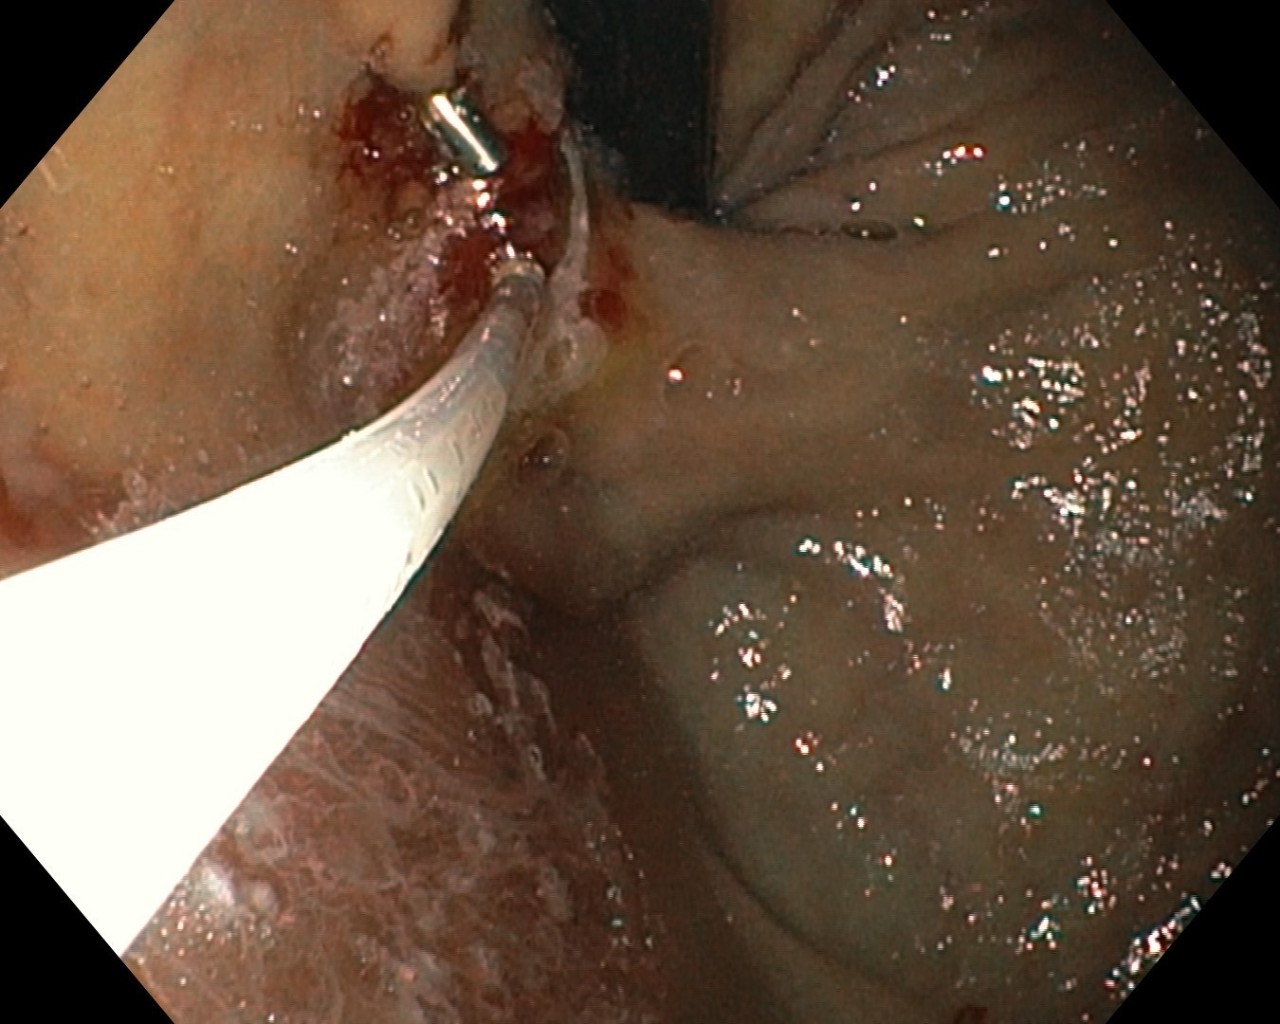

陈明仁和张宗胜主任立即带领胃镜室团队为患者行胃镜下治疗。经胃镜检查,确诊患者食管静脉和胃底静脉均发现破裂出血,找到出血灶后,医护团队通过细致谨慎的内镜操作和默契配合,成功为患者行胃镜下套扎及组织胶注射治疗。

▲胃底曲张静脉组织胶注射